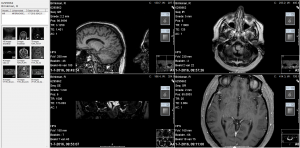

Na een intake gesprek met NKO arts Van Haesendonck-Gilles en professor Wuyts, heb ik mijn verzamelde medische gegevens, een gedetailleerde overzicht van de evenwichtsstoornissen vanaf 2012 tot heden en een ingevulde SO STONED formulier ter beschikking gesteld, zodat er een grote hoeveelheid gegevens aanwezig was omtrent mijn ziekteverloop. Vervolgens heb ik nog een uitgebreide gehoortest gedaan en tenslotte kreeg ik een bril op waardoor Floris mijn oog bewegingen kon zien door mij in een verschillende houdingen te plaatsen. Als er een vorm van duizeligheid of misselijk gevoel optreedt is het zichtbaar op het scherm (zie foto’s).

Bij de foto’s: Professor dr. Floris Wuyts onderzoekt mij en kijkt naar de oogbewegingen op het scherm.